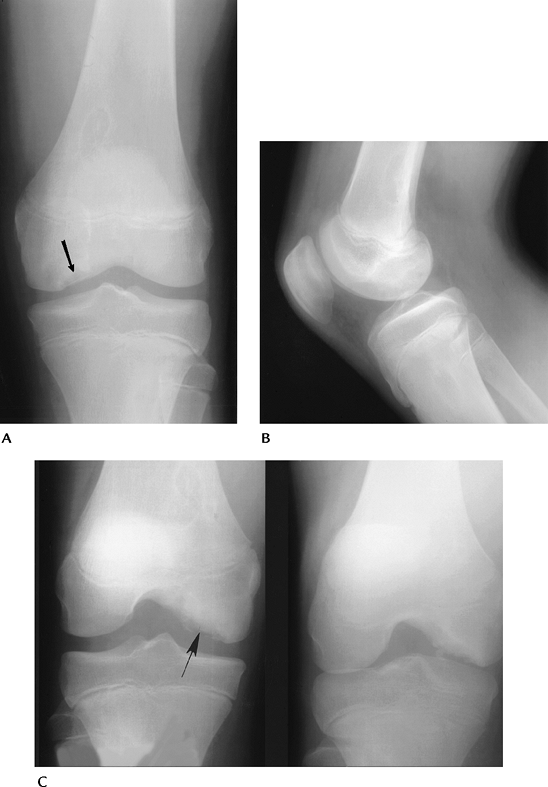

![]() |

FIGURE 5-56 AP (A), lateral (B), and notch views (C) demonstrating characteristic appearance and location of osteochondritis dissecans (arrow). Note the lesion is most easily appreciated on the notch view.